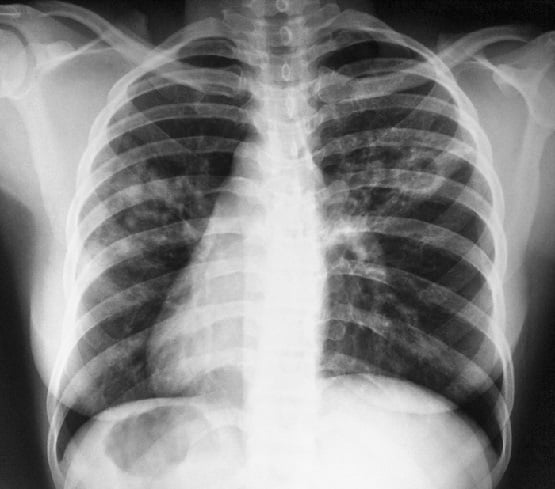

У взрослых туберкулёз лёгких может длительное время протекать бессимптомно или с малым количеством симптомов и обнаружиться случайно при проведении флюорографии или на рентгеновском снимке грудной клетки. Факт обсеменения организма туберкулёзными микобактериями и формирования специфической иммунологической гиперреактивности может быть также обнаружен при постановке туберкулиновых проб.

- Рентгенография.

Диагностика туберкулеза легких включает несколько этапов: медицинский осмотр, рентгенография грудной клетки, анализ мокроты на наличие бактерий и тесты на туберкулез, такие как проба Манту или интерфероновый тест. Эти методы помогают подтвердить или опровергнуть наличие заболевания.